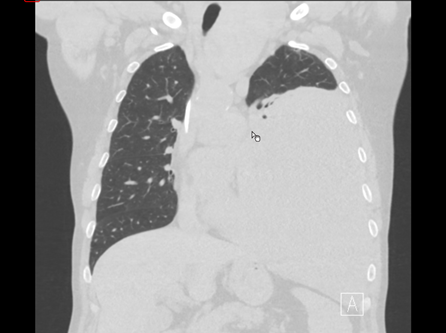

Präoperative Risikostratifizierung von Lungenherden unklarer Dignität mittels CDT-Test bei klinischem Verdacht auf ein Lungenkarzinom

• Klinische Validierung des CDT-Tests bei unklaren Lungenherden mit anschließender histologischer Analyse am operativen Resektionspräparat